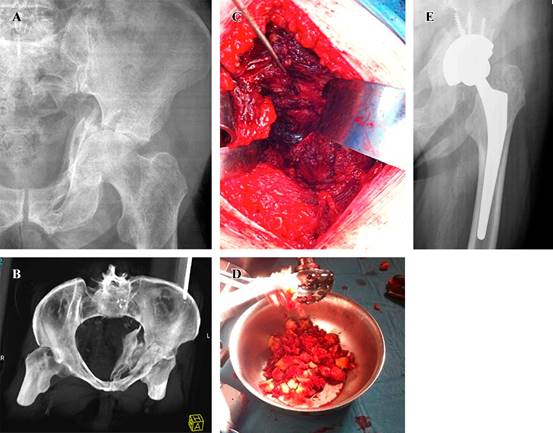

En cuanto al tipo de implante utilizado, en cinco casos se realizó reconstrucción con el concepto «CAGECUP» con una copa de tantalio multihole que permite fijar en múltiples direcciones, media de 56 mm (52-62), fijación con cuatro tornillos (3-5) con cabeza de 36 mm (Figura 1). Las otras dos fracturas requirieron de un implante de reconstrucción tipo anillo de Burch-Schneider (inserto 44 mm, cabeza 28 mm) por elección del cirujano principal debido a que eran fracturas con mayor inestabilidad, un caso de ambas columnas y en una de columna anterior y hemitransversa posterior por el desplazamiento ocurrido entre fragmentos (Figura 2). En todos los casos se utilizó autoinjerto de cabeza de fémur, en uno de los cuales se asoció además a sustituto óseo DBX® (Depuy Synthes) más chips de esponjosa por considerarse autoinjerto cuantitativamente insuficiente. Se implantó vástago cementado en cuatro casos y no cementado en tres (Tabla 2).

Figura 1: A) Radiografía anteroposterior (AP) de pelvis con fractura de columna anterior y hemitransversa posterior. B) Reconstrucción 3D de tomografía axial computarizada de pelvis. C) Visión del fondo acetabular a tres semanas postfractura desde un abordaje lateral. D) Injerto de cabeza femoral en la zona medial. E) Radiografía AP de pelvis con consolidación completa a tres meses postoperatorios, utilizando acetábulo de tantalio y vástago no cementado.